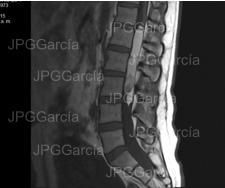

Estudio de resonancia magnética prequirúrgico que demuestra

una lesión tumoral torácica relacionada a un meningioma

RESECCIÓN MICROQUIRÚRGICA DE MENINGIOMA TORÁCICO

Estudio de resonancia magnética prequirúrgico que demuestra una lesión tumoral torácica relacionada a un meningioma